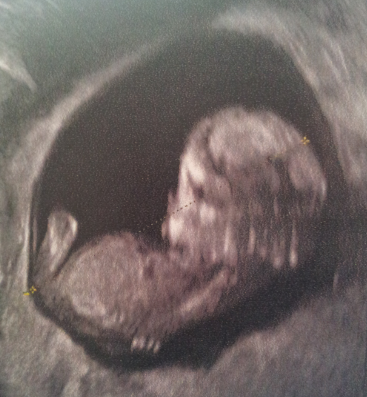

Alors bébé va bien. Au début de l'écho il dormait tête en bas, mais ça a pas duré! La vraie bamboula là-dedans. Impossible de lui mesurer la nuque au départ tellement il bougeait. Elle le titillait avec l'appareil en disant tourne toi du coup il a pris mon utérus pour un trampoline. Il appuyait ses pieds contre la paroi et faisait des sauts pas possible. Puis après il avait décidé de faire des coucou en se cachant derrière ses bras... Bref elle a dû finir en vaginal pour le "coincé" et prendre les mesures de la nuque.

Puis elle a retenté une mesure en abdominal mais il lui a montré ses fesses!!! Au final elle a quand même pu prendre toutes ses mesures tête ventre nuque fémur etc etc.

On a pu entendre son coeur.

Oui j'ai une feuille avec les mesure du crâne, du ventre, du fémur etc etc et la longueur cranio codale est de 5,43cm donc elle m'a dit parfait!

À y'a une petite différence moi il fait 6,10 cm